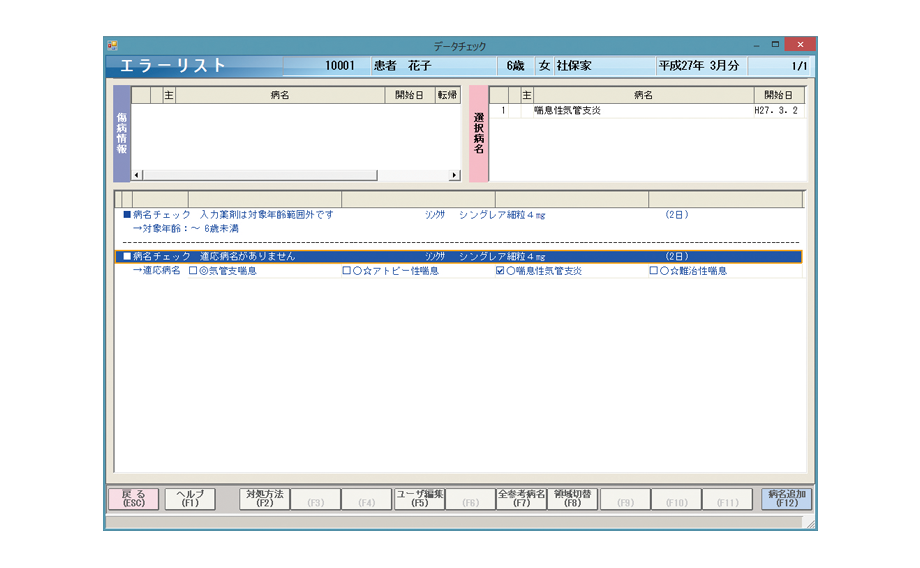

メディコムが誇る病名チェック機能

レセプト審査が厳格化される中、レセプト病名をチェックする機能は益々重要となっています。

さらに「突合点検」に対応するため、メディコムでは、レセプト病名の登録漏れだけでなく、投与量や投与期間、年齢などもチェックできます。

※投与量・投与期間のチェックについては、プロトンポンプ阻害剤(PPI製剤。タケプロンやオメプラゾールなど)のみチェック可能です。

※年齢のチェックについてはモンテルカスト製剤(シングレアやキプレス)のみチェック可能です。